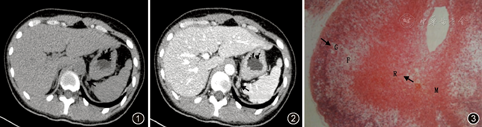

7例均行CT检查,示一侧肾上腺直径0.9~3.0 cm单发结节,平扫CT值–2~21Hu,增强后1例无明显强化,其余6例强化程度与结节周围腺体相似,CT值32~99Hu(图1,图2)。5例行B超检查,1例可见一侧肾上腺增大,回声欠均,其余3例未见异常。4例行131I –MIBG肾上腺髓质显像,1例24 h后可见一侧肾上腺区示踪剂异常浓聚,3例未见异常。2例患者行MRI检查未见异常。

7例患者均行手术治疗,2例术前疑诊为嗜铬细胞瘤的患者常规行2~4周术前准备,主要应用α、β–肾上腺素能受体阻滞剂、钙离子拮抗剂等控制血压、心率在正常范围;3例疑诊为肾上腺皮质腺瘤(2例醛固酮腺瘤、1例库欣腺瘤)及2例不明结节(131I–MIBG均阴性)患者均直接行手术治疗。术前计划行肾上腺病变部分切除,术中探查3例发现肾上腺呈多发结节状,1例未发现明确病变,行一侧肾上腺切除,其余3例术中可探及明确结节行肾上腺部分切除,3例行开放手术,4例行腹膜后腹腔镜手术。患者术中血压波动较平稳,最大收缩压150~205 mmHg,收缩压波动值45~85 mmHg,舒张压最高90~125 mmHg,舒张压波动值25~50 mmHg,手术时间70 ~130 min。术后病理检查显示单纯肾上腺髓质增生5例,髓质增生合并皮质库欣腺瘤及皮质增生各1例。镜下见肾上腺髓质增多,髓/皮质比值1∶2~1∶6,肾上腺尾部及两翼可见髓质侵入,伴或不伴结节形成(图3)。术后行依据病理提示行多发性内分泌肿瘤(MEN)2相关排查如甲状腺、甲状旁腺、胰腺等相关功能及影像学检查除外MEN,2例患者行基因检测未发现Ret基因位点突变。随访4~162个月,所有患者术后血压均有下降,合并库欣腺瘤的患者术后3个月血压完全恢复正常,其他患者血压仍高于正常,需用降压药物种类及剂量较手术前均减少,1例患者术后2年随诊发现对侧肾动脉狭窄,扩张治疗后血压进一步改善。术后3个月复查24 h尿儿茶酚胺1例术前增高的患者无明显下降,其余患者未见异常。复查24 h尿游离皮质醇、131I–MIBG、CT均未见明显异常。